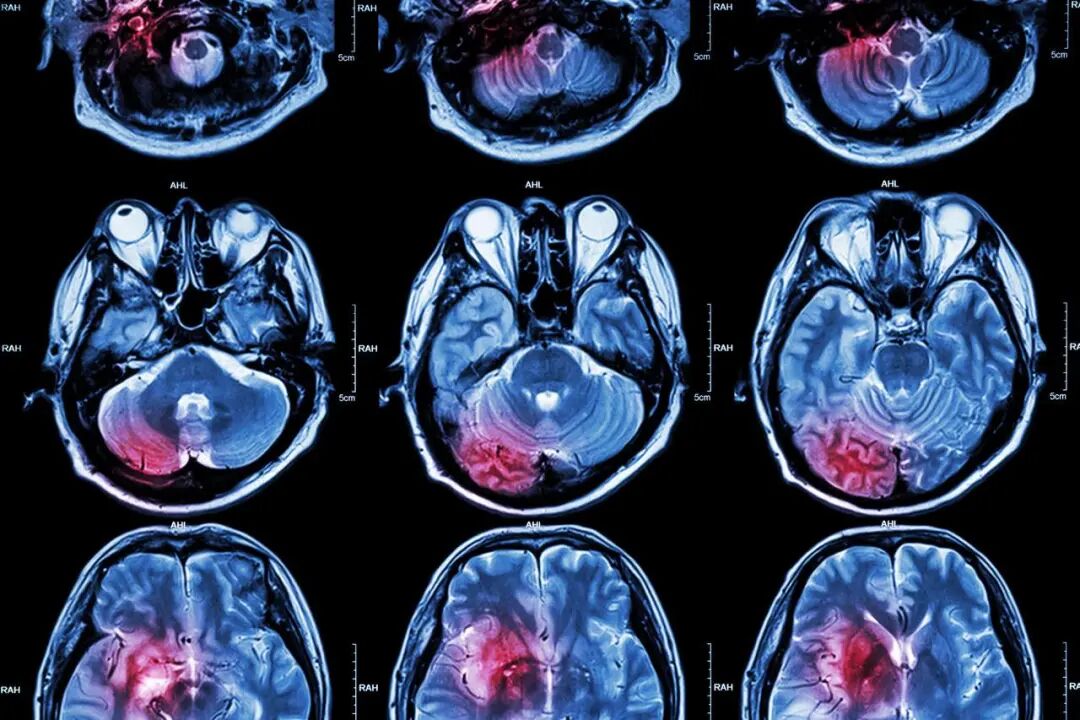

脑梗死,即缺血性脑卒中,是一种局部脑组织血液循环障碍导致缺血、缺氧性坏死的疾病。

一旦发生脑卒中,会给患者大脑造成不可逆的损伤,严重影响健康和生命。

脑梗死的后果不容忽视,它会给患者带来永久的身体残疾,严重者甚至可能导致死亡。

由于大脑的重要性,脑梗死的发生往往导致智力、言语、感觉、运动等多方面功能的丧失,严重影响患者的生活质量和家庭幸福。